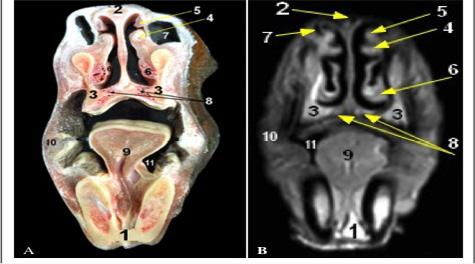

Cross sectional anatomy (Panel A) and MR image (Panel B) of horse head at the level of body of mandible. 1) Body of mandible; 2) Nasal bone; 3) Maxilla bone; 4) medial accessory nasal cartilage at Alar fold; 5) Straight fold; 6) Basal fold; 7) False nostril (Nasal diverticulum); 8) Vomeronasal organ; 9) Tongue; 10) Buccinators muscle; 11) Sublingual recess.